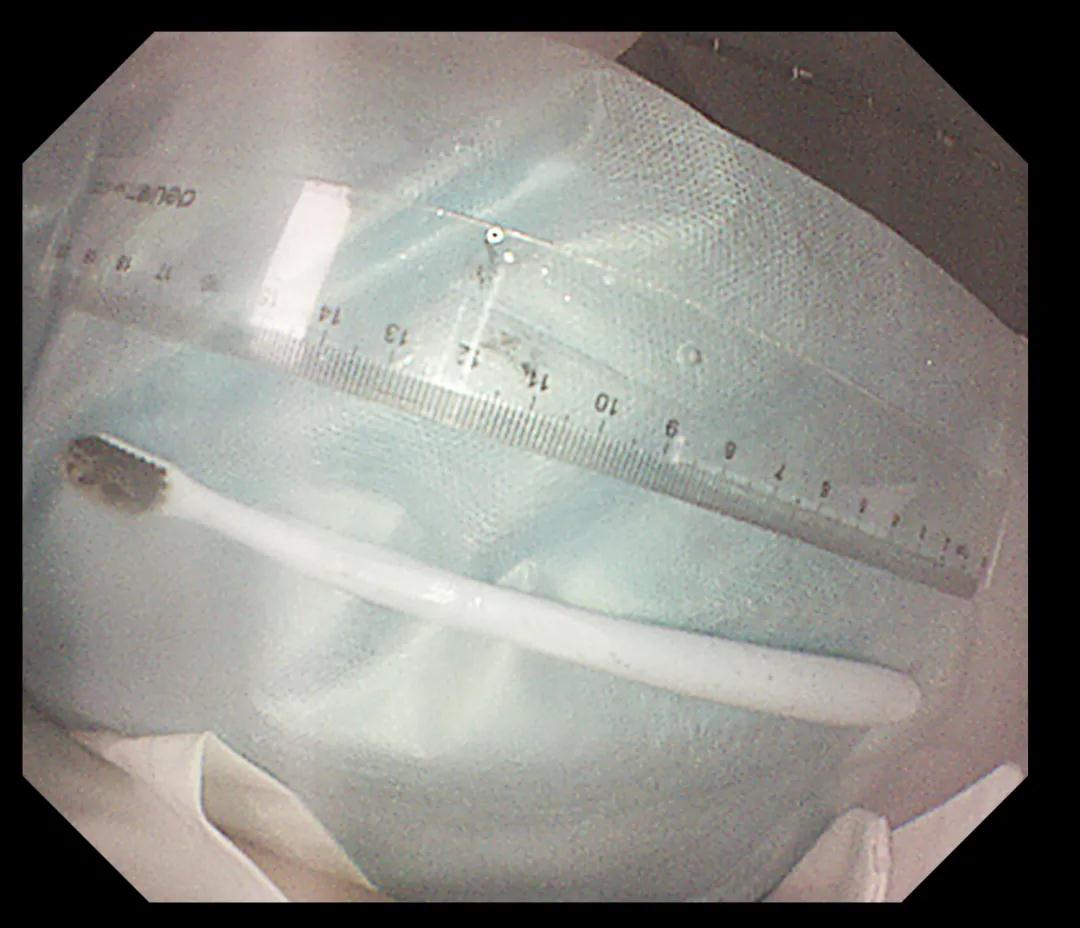

經(jīng)過反復努力嘗試,圈套器終于緊緊的套住異物,使牙刷長軸盡量與食道長軸平行,適當注氣擴張食道腔。經(jīng)過不懈努力,順利將其取出,取出牙刷經(jīng)測量長度約20cm,似乎這條細細的胃鏡就是一條連接希望的生命線。此時在場所有人懸著的那顆心也終于落下。術后小楊癥狀逐漸消失,生命指征平穩(wěn),情緒也平靜下來。